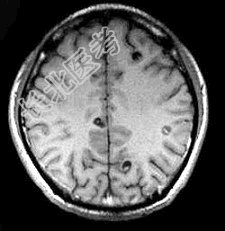

- 单项选择题患者,男, 29岁。头痛不适半个月。MRI扫描如图示。据此可作出下列最可能的诊断是 ( )

A、脑囊虫病

B、脑弓形虫病

C、脑结核

D、脑转移瘤